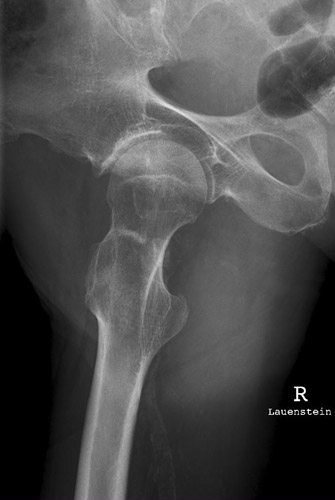

Lauenstein

117_2.jpg

Fehler

Die obere Begrenzung des Trochanter majors reicht fasst bis zum Hüftkopf. Er überdeckt zum Teil den Schenkelhals und dessen distalen Teil. Der Trochanter minor bildet sich weit unterhalb des Trochanter major im Schaft des Oberschenkels, randbildend, ab. Der femur wurde zu weit abgespreizt. oder fast seitliche Lagerung der Oberschenkels. Nicht die Oberschenkelachse soll zur Filmachse parallel stehen, sondern die Achse des Schenkelhalses.

Abhilfe

Der Patient darf den Femur nur wenig nach außen abspreizen, damit stellt sich der Schenkelhals horizontal ein.